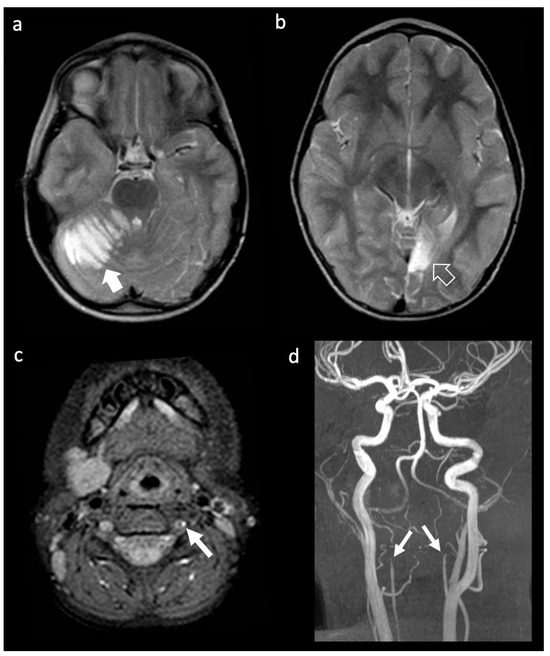

Background: Heterozygosity for pathogenic variants in the ABCC6 gene has been associated with an increased incidence of cerebrovascular diseases. This study aims to characterize the prevalence and clinical and neuroradiological phenotypes associated with monoallelic and biallelic ABCC6 variants in pediatric and adult patients presenting with arterial ischemic stroke or cerebral small vessel disease (CSVD). Methods: We conducted a retrospective observational study on 143 consecutive patients (48 pediatric, 24 juvenile, 71 adult) diagnosed with ischemic stroke or CSVD of unknown etiology. Clinical and neuroradiological data were collected and analyzed in relation to the identified genetic variants through next-generation sequencing. Results: Among the patients, 16 (11.2%) tested positive for causative variants in the ABCC6 gene, with 11 subjects carrying monoallelic variants and 5 carrying biallelic variants. Patients with biallelic variants exhibited severe and complex vasculopathy, with a high incidence of early ischemic events. In contrast, monoallelic carriers predominantly presented with microvascular disease manifestations, including lacunar strokes and signs of CSVD. Conclusions: The results suggest a significant age-dependent phenotypic divergence in patients with ABCC6 variants, highlighting the impact of heterozygosity on cerebrovascular health. Identifying these variants may enhance risk stratification and inform management strategies in patients with traditional vascular risk factors. Full article